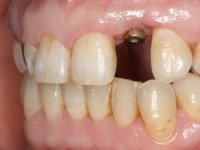

• Placement of an implant at the tooth site 2.2. Rehabilitation of the implant with a coronary and gingival component abutment. in which the screw access hole was "camouflaged" with a feldspathic veneer.

Treatment began with re-preparation of the cast post and core, with the purpose of placing the cervical finishing lines with an intra-sulcular location and simultaneously making a suitable temporary crown. With a very simple orthodontic treatment, the diastema was closed between the upper central incisors, and this position was stabilized with a wire placed on the palatal surface of the central, functioning as containment. Later, a slow orthodontic traction of tooth 2.2 was attempted, in order to reduce, although very slightly, the vertical bone loss in this area. At the end of the traction, tooth 2.2 was extracted and the area was provisionally rehabilitated with a composite resin crown bonded to the adjacent teeth. A dental implant was placed in the area of tooth 2.2 and the temporary crown was again bonded to resin, provisionally rehabilitating the patient during osseointegration. In tooth 1.3 a gingivectomy with an electric scalpel was performed, with the intention of raising the cervical level of 1.3 achieving greater harmony with tooth 2.3. Stabilized soft tissues were impressed using the open tray technique with putty and light addition silicones. Collection of the color of both the dental component and soft tissues was done by the ceramist in the office. In the laboratory, the impressions were transferred to plaster and gave origin to work models that were properly analyzed. It was decided to assemble a metal-ceramic abutment screwed onto the implant. This abutment was cast with a noble alloy and subsequently coated with coronary and gingival ceramics. Due to the inclination of the implant, the screwing inevitably conditioned the exit of the screw hole through the vestibular surface. In order to conceal this situation, the design of the abutment has already been conceived with the intention of accommodating on the vestibular surface the bonding of a feldspathic veneer. This abutment was tested in the mouth and adjustments were made in the gingival ceramic component. Its adaptation to the soft tissues was done in a subtractive way, with a drill, as well as additive, adding resin composed of gingival tonality.

This addition of resin would guide the ceramist in the final placement of the gingival tonality ceramic. The crown that would rehabilitate tooth 1.3 was cemented in this test session with glass ionomer cement, reinforced with composite resin. Once the laboratory work was finished on the veneer for tooth 1.2, the abutment, and the veneer for the implant, this was bonded in the mouth, after placement of the absolute insulation. The work completely satisfied the patient. For eight years, the patient had periodical check-ups, and was pleased with the treatment, but also began to show interest in an aesthetical intervention on the upper central incisors. Once the second phase of our intervention was decided, dental preparation of teeth 1.1 and 2.1 was performed for the placement of two feldspathic veneers. Particular care was taken in the distal inter-proximal preparation adjacent to the abutment of the implant.

The axis of insertion of the veneer in relation to the abutment was very carefully evaluated. The feldspathic veneers were prepared in the laboratory and then bonded to the mouth after placing absolute insulation. One year later, we began our third phase of treatment, after the veneer in tooth 2.1 fractured. A dental preparation was done on the bonded veneer, seeking to extend the distal inter-proximal interface more to the palate. The objective would be to move the veneer to a more palatine contact point. Preparation of tooth 1.2 was limited to creating an insertion axis. After preparation, the total crown and laboratory veneer were bonded to the mouth. First, the crown was bonded using a relative insulation with Teflon, later the veneer was bonded after the absolute insulation placement. In the crown, I used this type of insulation to avoid the use of staples. It would be difficult to apply due to the shape and size of the tooth, and would also be aggressive to the soft tissues. After bonding procedures, the occlusal integration of the work was evaluated.